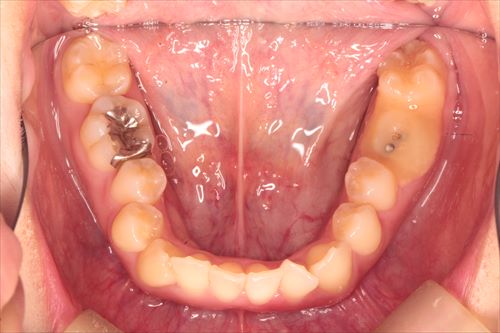

下あごの咬合面観です。

下あごに関しては、埋まっている8番(親知らず)を切開して抜歯しました。

下あご咬合面観です。